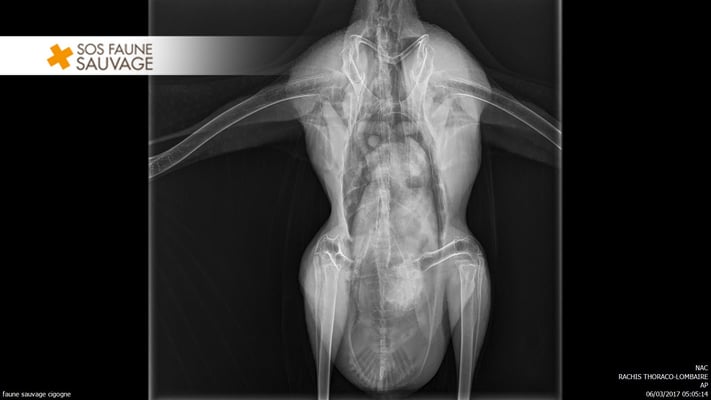

D’autres animaux ont été surpris par des rafales de vent, les entraînant violemment contre des baies vitrées ou encore contre des pilonnes électrique : c’est ce qui est arrivé à la cigogne blanche que nous avons recueillie au Centre suite à la tempête. Cette dernière souffre d’une fracture de la clavicule. Soignée par notre vétérinaire Capvéto Guéret, elle devra garder l’aile immobilisée pendant plusieurs semaines avant d’entreprendre une rééducation tout aussi longue.